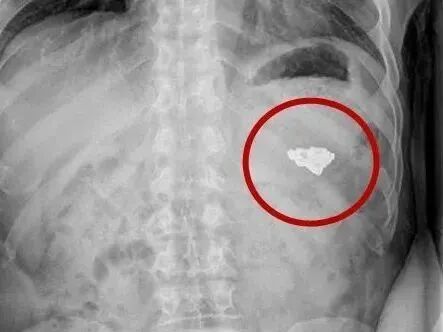

- (图片来源于网络)胃癌在发生的过程中因为没有什么特异的症状,所以不容易发现。即便有一些症状,可能仅仅是胃痛、食欲不振、腹部不适等,这些症状极易与胃炎、胃溃疡等胃病相混淆,因此难以察觉。所以有些胃癌...